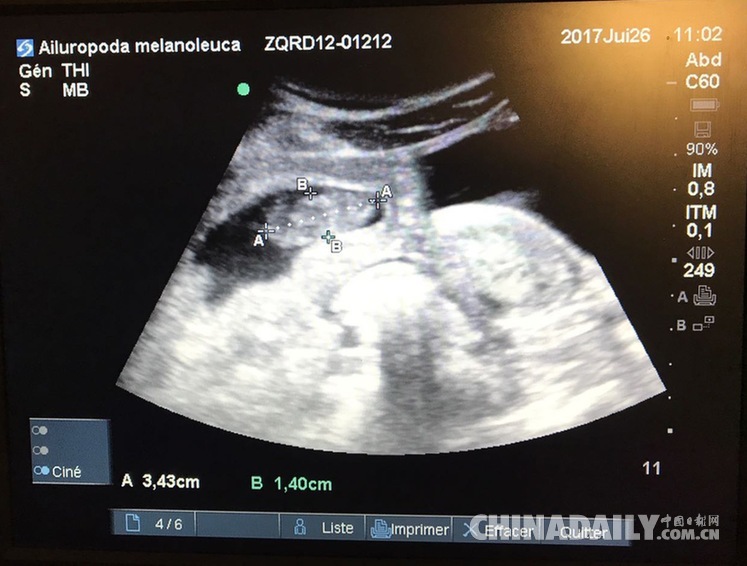

旅居法國熊貓產(chǎn)雙胞胎 一只存活狀態(tài)很好

9歲的大熊貓“歡歡”在接受最新B超檢查時發(fā)現(xiàn)懷上雙胞胎。